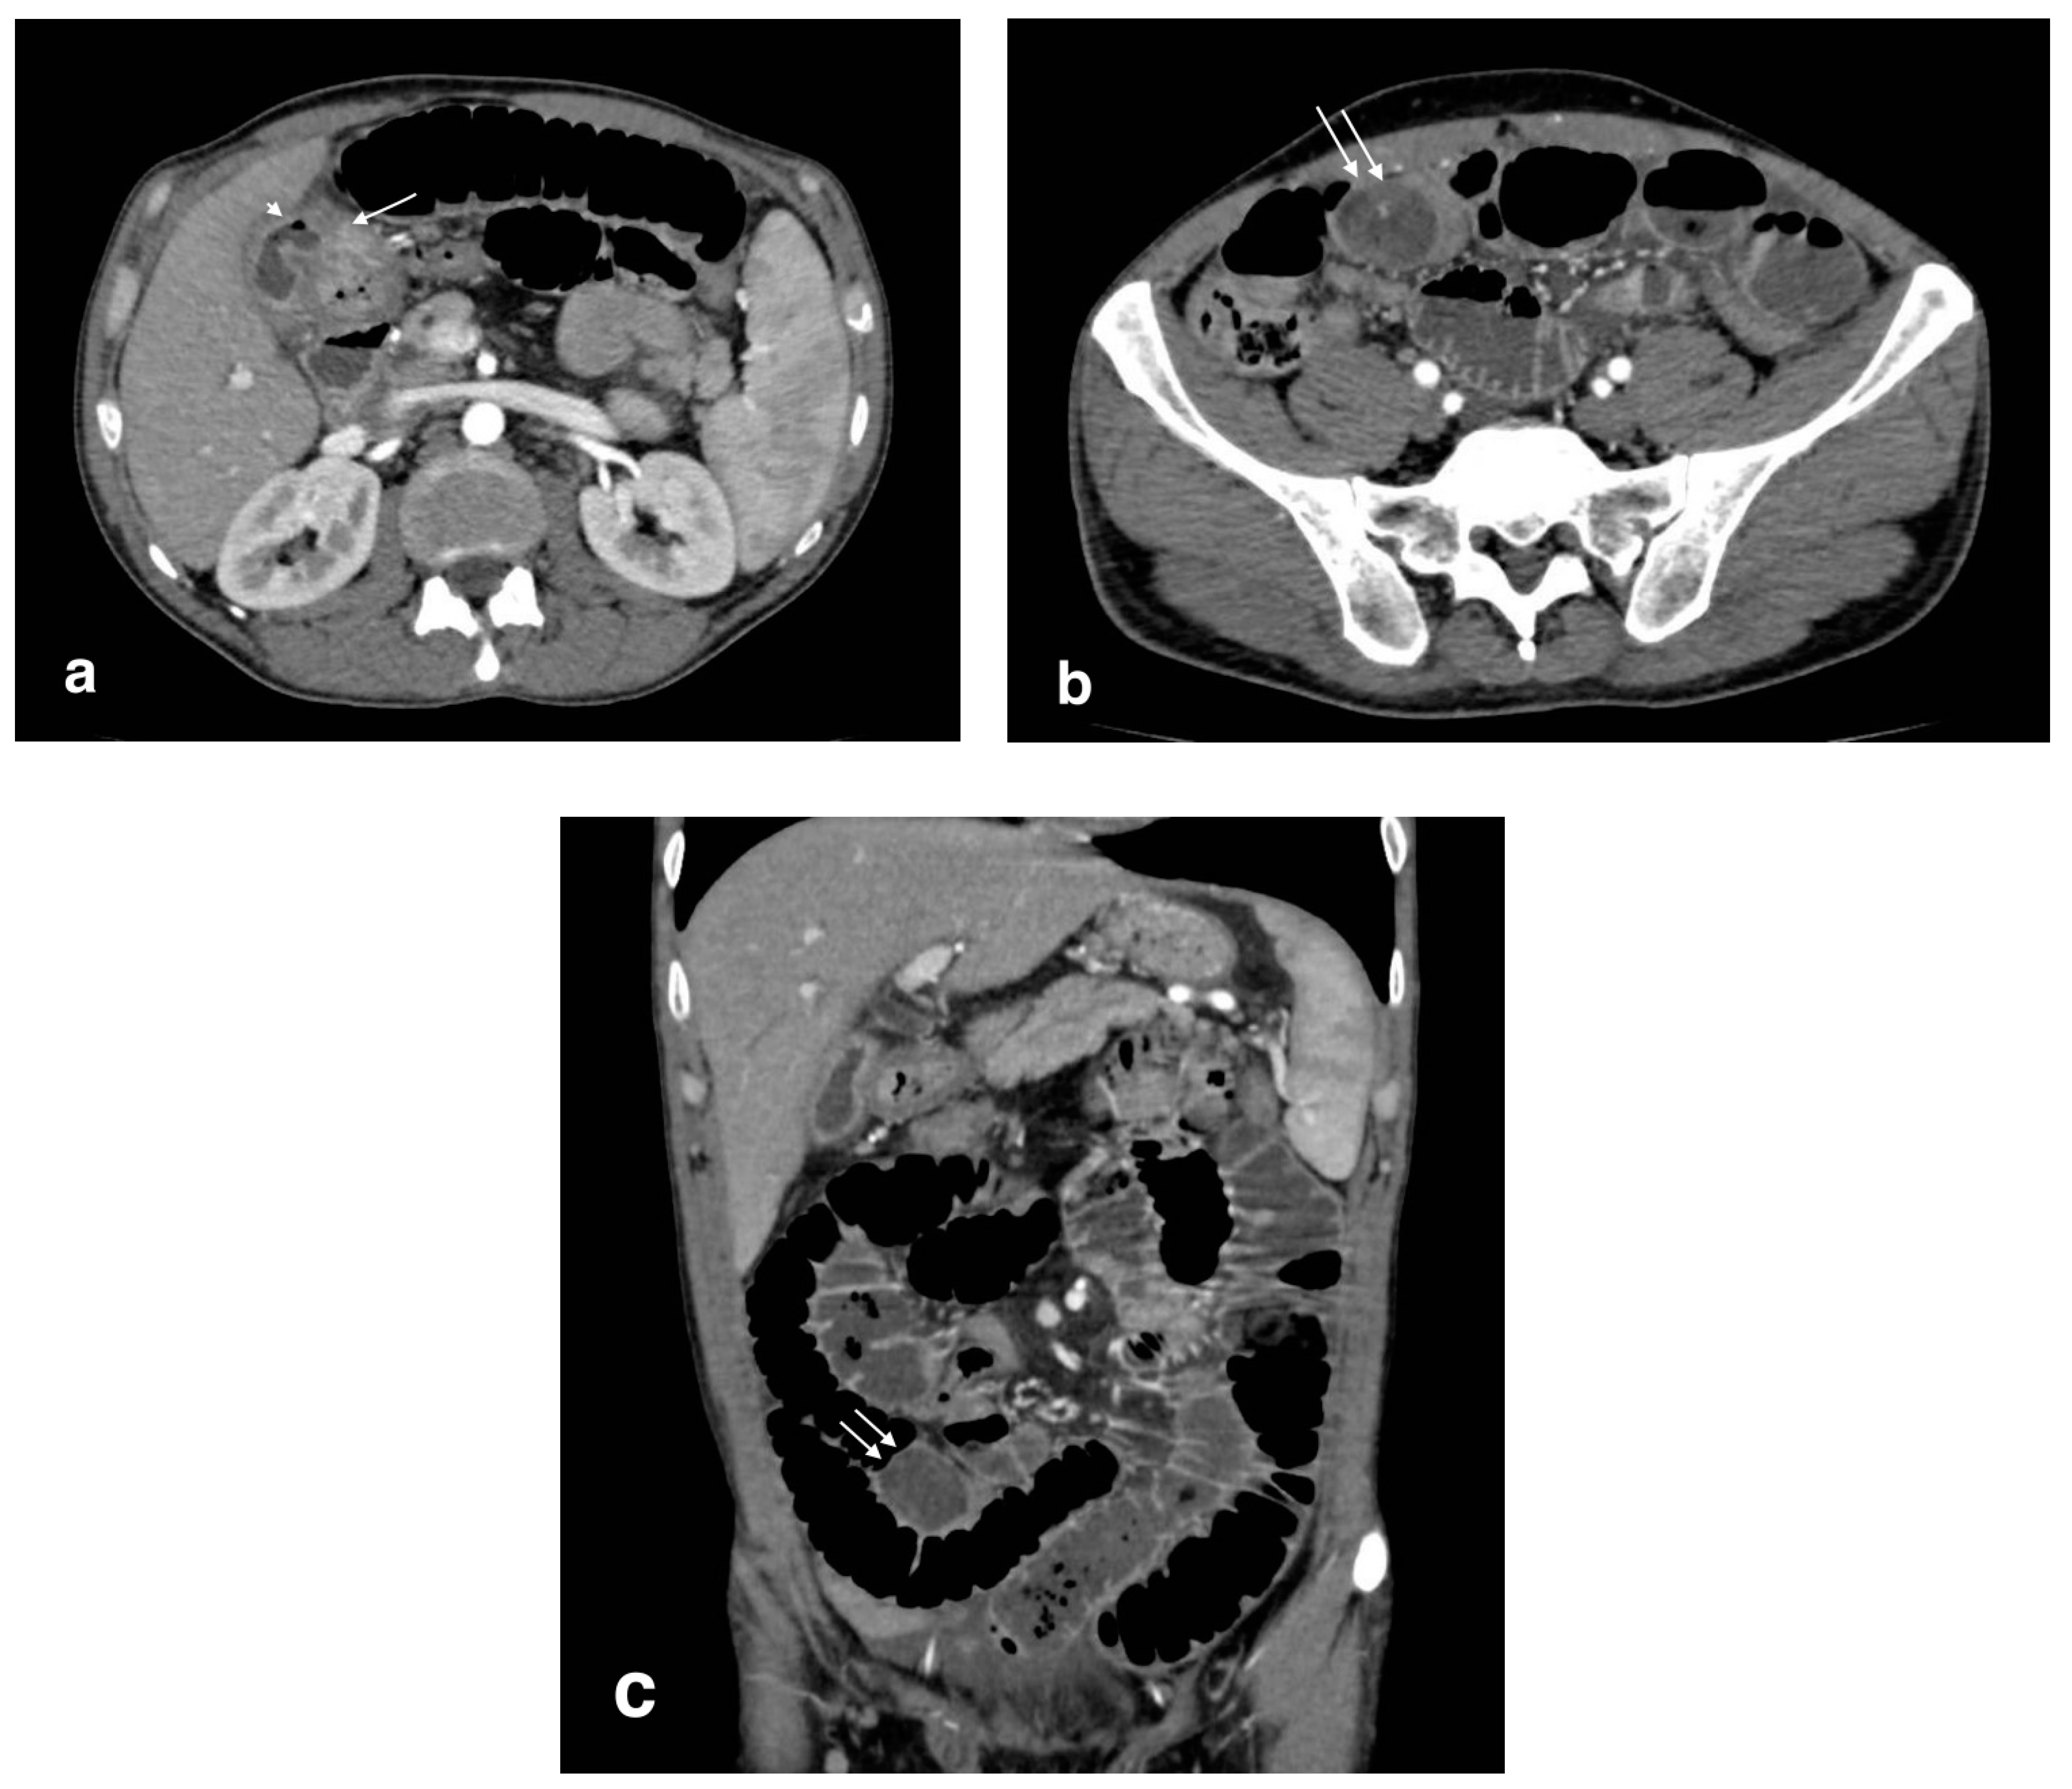

Figure 6.

Bilioenteric fistula (biliogastric) with gallstone ileus: (a): cholecystogastric fistula (arrow) with the presence of air in the gallbladder lumen (arrowhead); (b) axial image shows a large gallstone in the ileum (arrows) with small bowel overdistension (white arrows); (c) coronal image demonstrates an obstructive gallstone in the ileum (arrows) with small bowel overdistension.